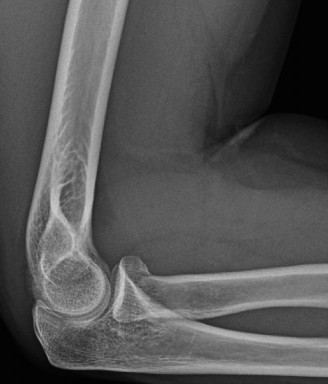

A 42-year-old female presents to the office for follow up after sustaining a minimally displaced radial head fracture 3 months prior. She states she was initially treated in long-arm splint by the ER and did not follow up with an orthopaedic surgeon until now. Per her report, she removed the splint 4 weeks after the injury, but did not move her elbow due to pain. She now has no pain but is unable to reach that hand to her face or head. The remaining history is significant for previous ulnar nerve surgery for which she is unable to provide details. On physical examination, her upper extremity is normal except for limited flexion/extension, measured to be 80 to 50 degrees by goniometer. In addition, she has a well-healed surgical incision about the medial elbow, consistent with a previous surgery on her ulnar nerve. Her images are shown (Figs. 2–82 to 2–84).

Figure 2–82